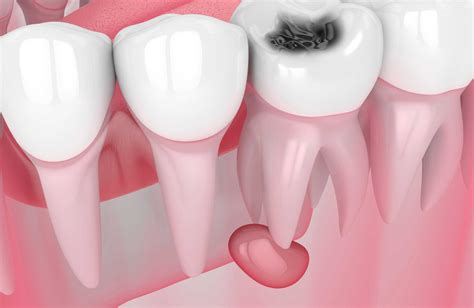

- Quiste radicular: Los más frecuentes, se encuentran en la punta de la raíz del diente y son provocados por caries que afectan al nervio dental.

La causa principal de los quistes radiculares es la necrosis pulpar, es decir, la muerte del tejido que se encuentra en el interior del diente (la pulpa). Los quistes periapicales están causados por la necrosis de la pulpa dental. Significa que el tejido blando situado debajo de la capa más dura y resistente del diente pierde su vitalidad, reduciendo el suministro de sangre, oxígeno y nutrientes. Infección bacteriana: La infección bacteriana en la raíz del diente es la causa principal de los quistes radiculares.

Si hay una caries que no ha sido tratada adecuadamente (o no ha sido tratada en absoluto). La caries ataca primero el esmalte del diente, luego la dentina, y poco a poco se extiende por el interior del diente, hasta la raíz. Es entonces cuando se forma el quiste.